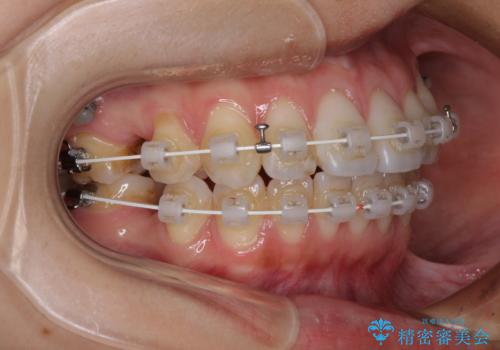

- 審美装置

- 八重歯と口元の突出感を気にして来院された患者様です。

歯列が前方に突出しており、上下の正中がズレていたため、左側は上下第一小臼歯を、右側は上下第二小臼歯を抜去し、ワイヤー装置による矯正治療を行うこととしました。

当初はインビザラインによる矯正治療をご希望でしたが、正中を合わせたいことや、口元の突出感を改善したいことから、ワイヤー矯正を強く推奨しました。

治療期間は2年に満たず、スッキリとした口元に仕上がりました。